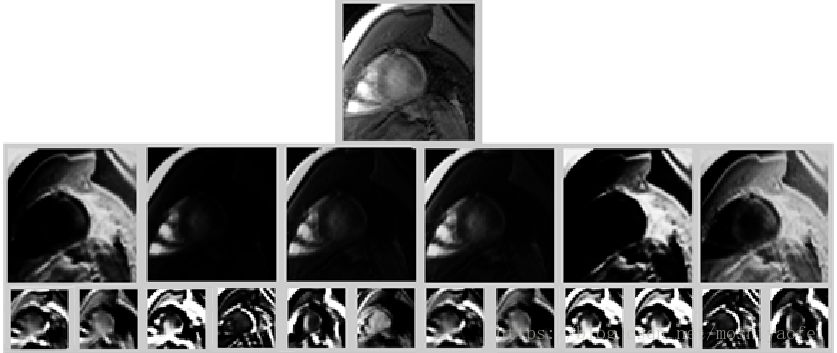

上面的架构(图1的结构)被发现是最简单的架构,可以直观地描述图像,如图3所示,很明显LV在输出图中有很好的描述。

Figure 3: the output maps after convolution; First row: the input Image. the second row: The output map of the first convolution layer after applying the 3x3 filters, third row: The output map of second convolutional layer after applying the 6x6 filters on each output map from the previous layers